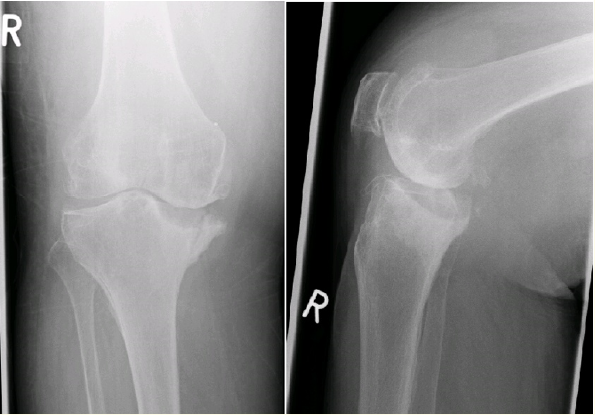

Soft Tissue Back Mass, Case Report

Abanoub Gabra, Mirza Baig, Alan Schiller, Mariam Gabra and Imran Baig. 5(11): 39-44.